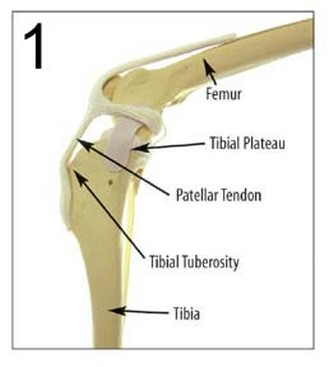

La stabilità dell’articolazione del ginocchio è dovuta anche ai legamenti crociati, che ne regolano i movimenti, prevenendo lo slittamento craniale o caudale della tibia sul femore, limitando la rotazione interna della tibia sul femore e opponendosi all’iperestensione del ginocchio.

Secondo alcuni studi sulla biomeccanica dell’articolazione del ginocchio l’inclinazione del plateau tibiale rispetto all’asse della tibia stessa rappresenta un fattore determinante nella patogenesi delle rotture del legamento crociato craniale. Tale inclinazione è responsabile dell’intensità della “spinta tibiale craniale”, ossia di quella forza, generata dalla compressione tra femore e tibia durante il carico ponderale, che provoca la traslazione craniale della tibia, più l’inclinazione è elevata, maggiore sarebbe la spinta craniale della tibia.